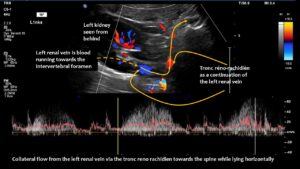

The main driving force was the compression of the left renal vein, as this vein transports most of the blood in the lower body hemisphere. Compression of this vein forces blood to run down the left ovarian vein towards the left internal and common iliac veins. The blood then tries to cross the spine to reach the inferior vena cava. This vessel returns blood to the heart. However, in this patient, the left common iliac vein was also compressed. Consequently, the increased pressure in the left renal vein could only be relieved by creating an additional collateral pathway. This connects the left renal vein with the spinal canal and is called tronc réno-rachidièn .

Large volumes of blood from the left renal vein enter the spinal canal and run along the spinal veins (epidural plexus) towards the skull, entering the intracranial sinuses. They can then leave the skull via the vertebral veins, but mainly via the jugular veins.